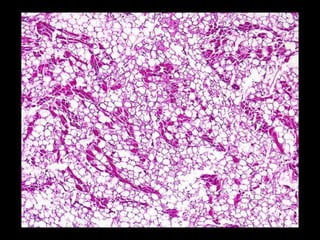

ESTEATOSIS (CAMBIO GRASO) •-Acumulación anómala de triglicéridos dentro de las células parenquimatosas.- •- Se observa con mayor frecuencia en el hígado (principal órgano implicado en el metabolismo graso) pero puede verse también en corazón, músculo y riñón.-

ESTEATOSIS (CAMBIO GRASO) •-Existen diversas causas (toxinas, malnutrición proteica [Kwashiorkor], diabetes mellitus, obesidad, hipoxia) pero la causa más común en adultos es el alcoholismo.- •- El significado del cambio graso depende de la causa y gravedad de la acumulación. La esteatosis es reversible per se.-